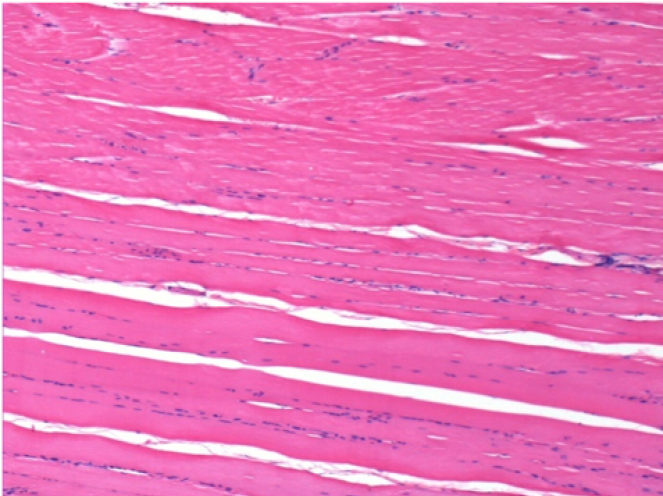

0,5 мл (5x 0,1 мл) підшкірна ін'єкція Ендопіл в праву підшкірну претибіальну ділянку.

П-90днів-ПШ-200X

П-210днів-ПШ-200X